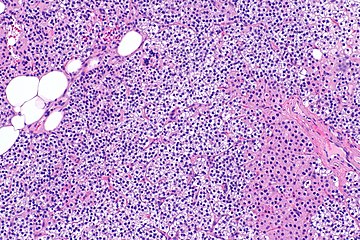

Parathyroid hyperplasia medium mag.

Primary hyperplasia of the parathyroid gland, results from both hypocalcaemia and increased phosphate levels by decreasing expression of calcium sensing receptors and vitamin D receptors at the parathyroid gland.[8][4] These decreases in receptor expression lead to hyperfunctioning of the parathyroid. Hyperfunction of the parathyroid gland is thought to exacerbate primary hyperplasia which evolves further to a secondary more aggressive hyperplasia. Histologically, these hyperplasic glands can be either diffuse or nodular.[24] Primary hyperplasia, usually resulting in diffuse polyclonal growth is manly related to reversible secondary hyperparathyroidism. Secondary hyperplasia of the parathyroid gland is more often a nodular, monoclonal growth that sustains secondary hyperparathyroidism and is the catalyst in the progression to tertiary hyperparathyroidism. Nodular hyperplastic glands in tertiary hyperparathyroidism are distinctly larger in both absolute size and weight up to 20-40-fold increases have been reported.[25][26][24]

Parathyroid glands are normally composed of chief cells, adipocytes and scattered oxyphil cells.[27][14] Chief cells are thought to be responsible for the production, storage and secretion of parathyroid hormone. These cells appear light and dark with a prominent Golgi body and endoplasmic reticulum. In electron micrographs, secretory vesicles can be seen in and around the Golgi and at the cell membrane. These cells also contain prominent cytoplasmic adipose.[27][14] Upon onset of hyperplasia these cells are described as having a nodular pattern with enlargement of protein synthesis machinery such as the endoplasmic reticulum and Golgi. Increased secretory vesicles are seen and decreased intercellular fat is characteristic.[27][24] Oxyphil cells also appear hyperplasic however, these cells are much less prominent.[citation needed]